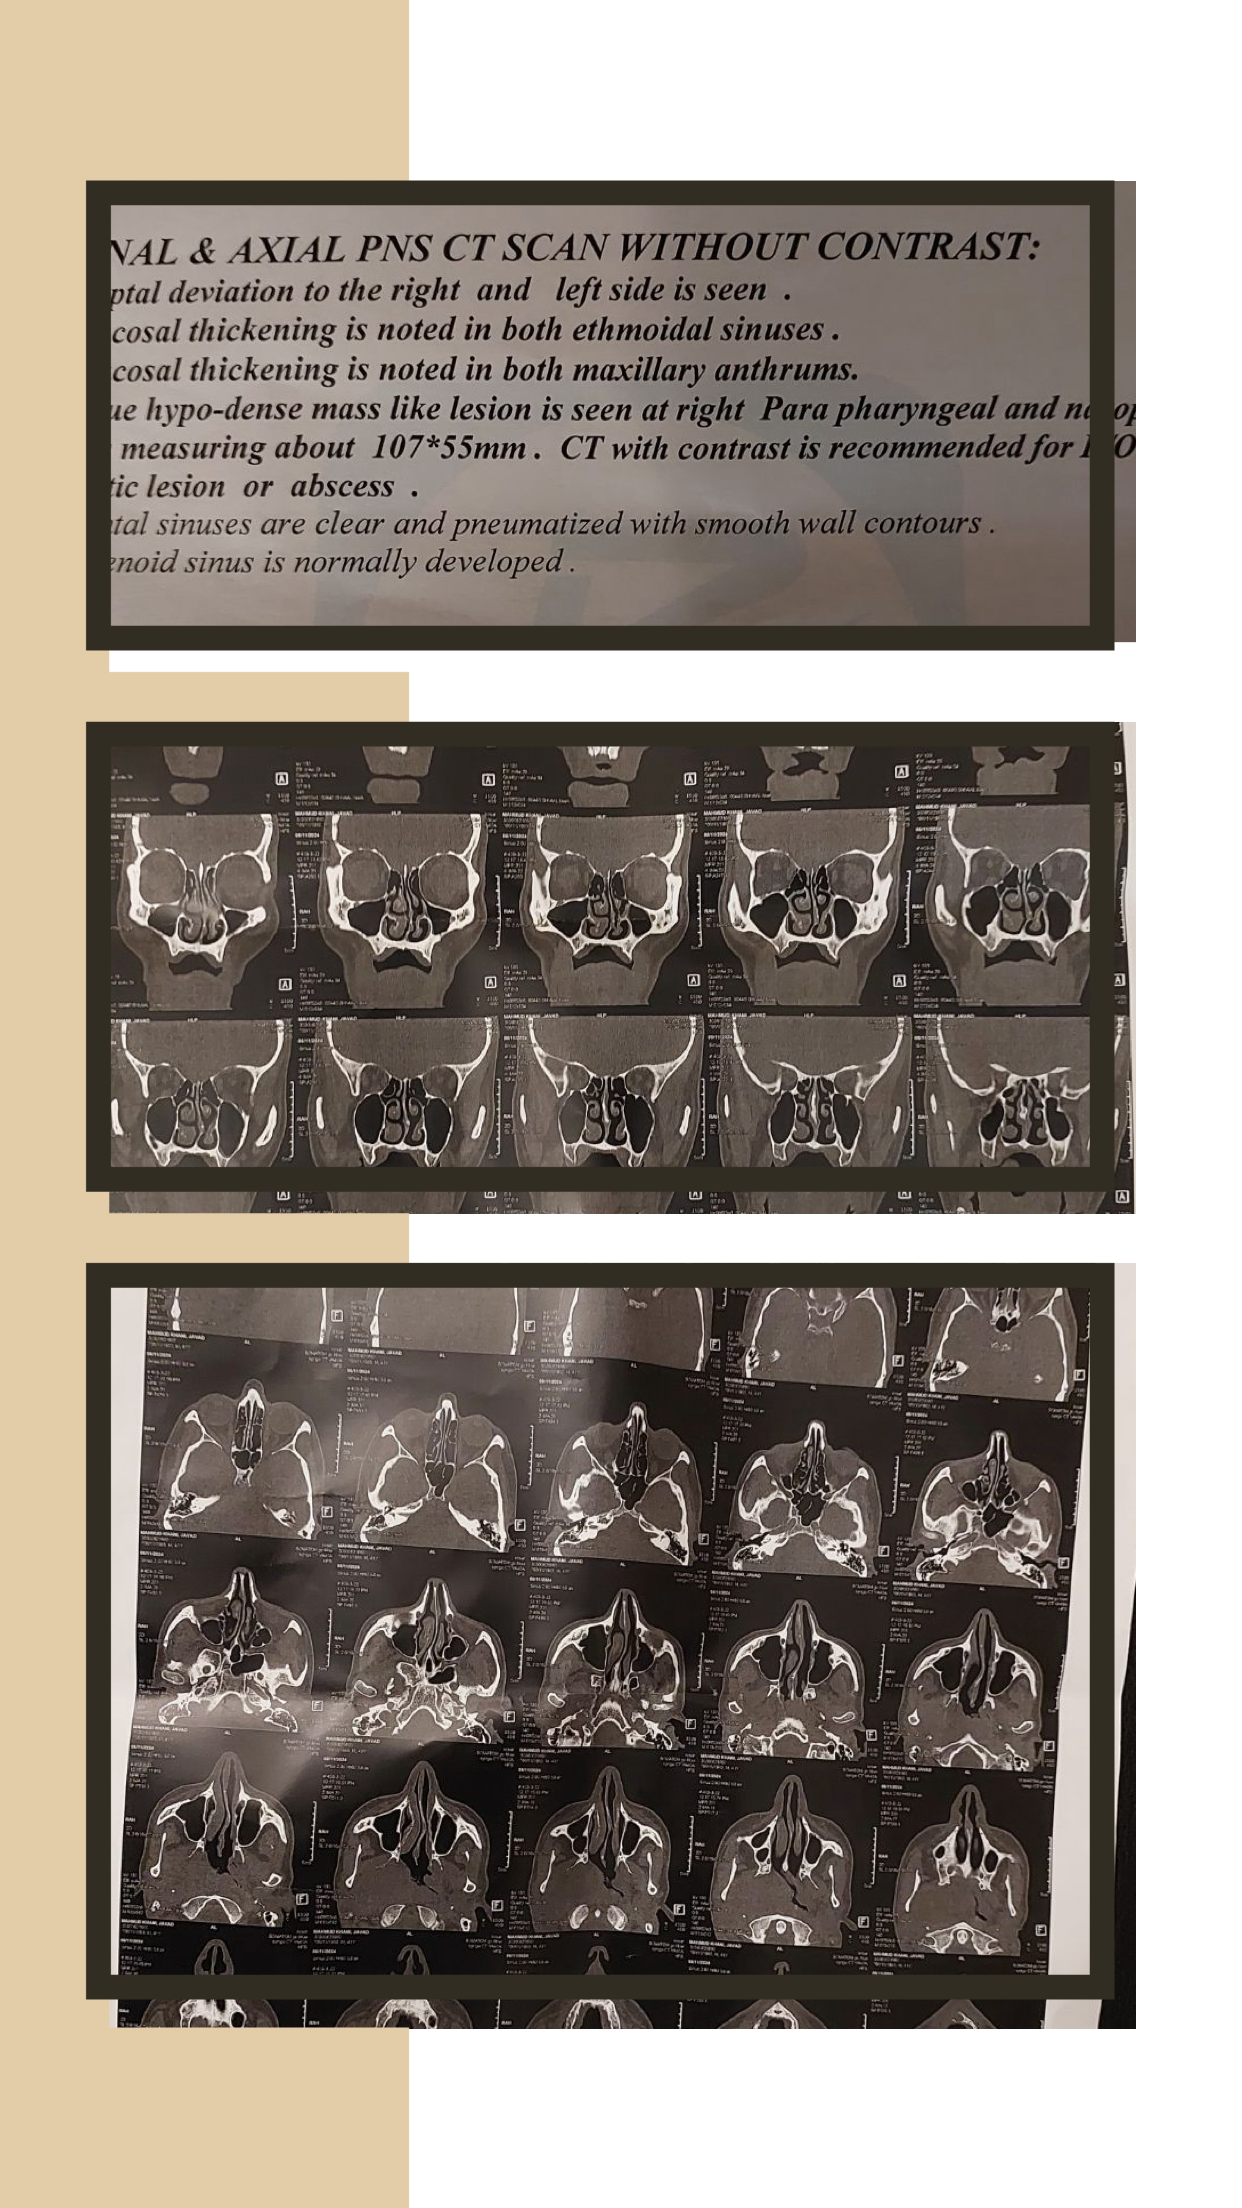

The patient was a forty-year-old man who could not speak easily . He had a nasal voice , and in order to speak with a more expressive voice he bent his head forward especially to pronounce long vowels . From the beginning , it was clear that he must have a blockage in his mouth […]